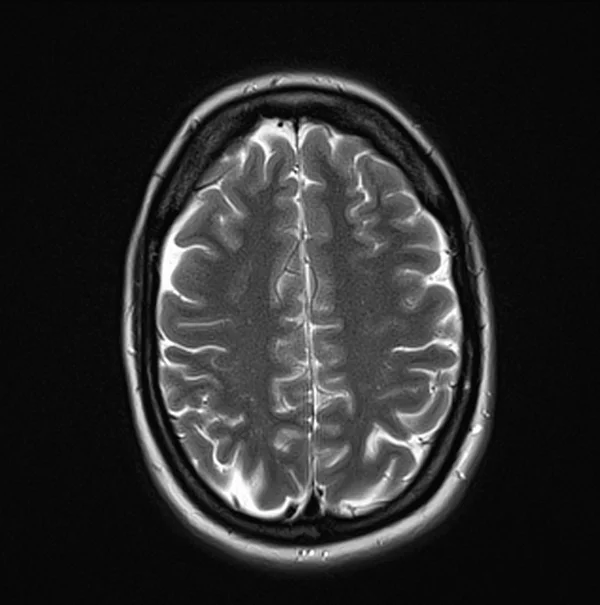

Brain MRI T2 axial images